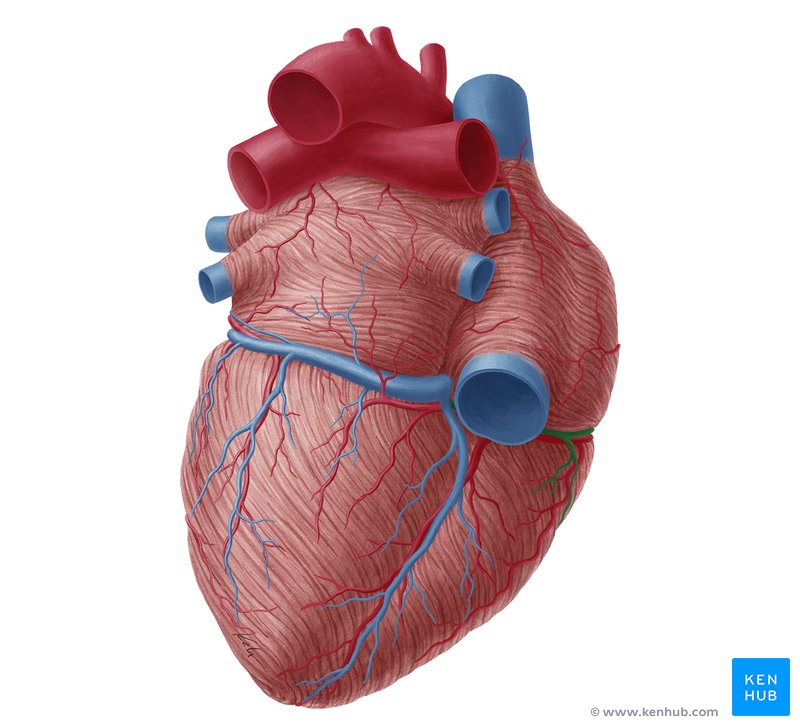

Anterior Interventricular Artery

Circumflex Branch

Coronary Artery

Coronary Sinus

Anterior Interventricular Sulcus

Coronary Sulcus

Small Cardiac Vein

Anterior Cardiac Vein

Marginal Branch

Circumflex Artery

Great Cardiac Vein